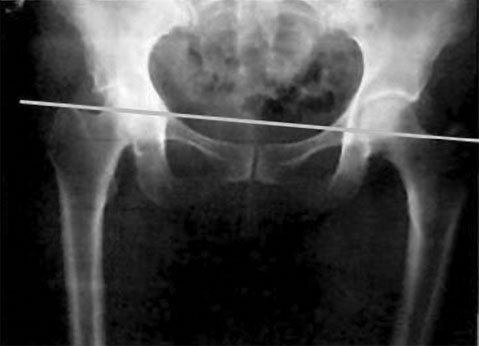

Симметрию тазовых суставов во фронтальной плоскости (на виде спереди) можно увидеть на рис. 15.

Рис. 15. Симметрия тазовых суставов

А теперь сравните его с рис. 16 – горизонталь, идущая по ним, перекашивается к левой ноге.

Рис. 16. Асимметрия таза

Видно, что уровень левой стороны (реальной стороны человека) ниже, чем правой. Значит, левая нога больше опирается на землю. Именно здесь нас поджидает дисбаланс под названием «опорная нога». На опорную ногу при ходьбе приходится бо?льшая часть веса человека.